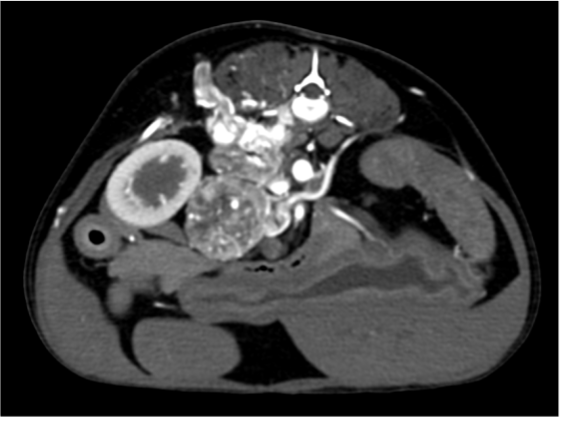

복부 장기 정밀 확인

복부 장기의 변화와 종괴를 단면으로 확인하는 데 도움됩니다.

(참고사진 : 복부 종괴가 의심되는 환자의 CT 영상)